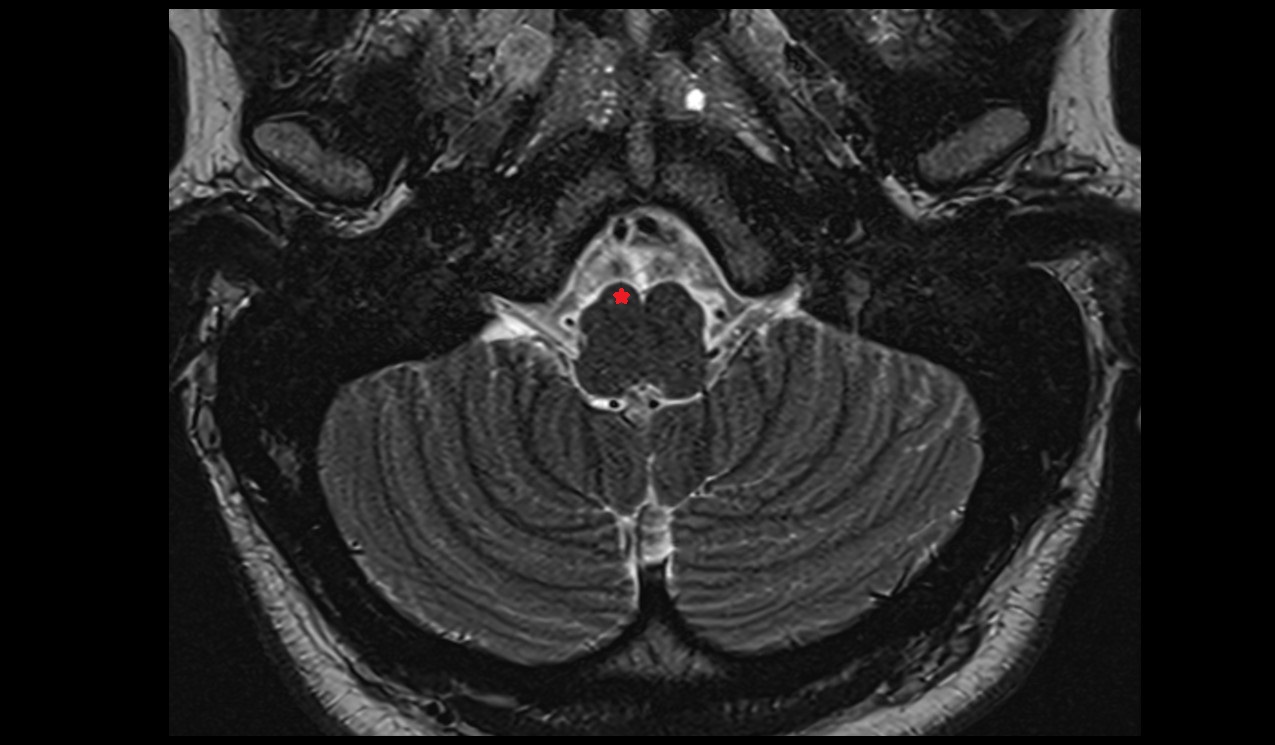

- Pons

- Raphe of pons

- Transverse pontine fiber